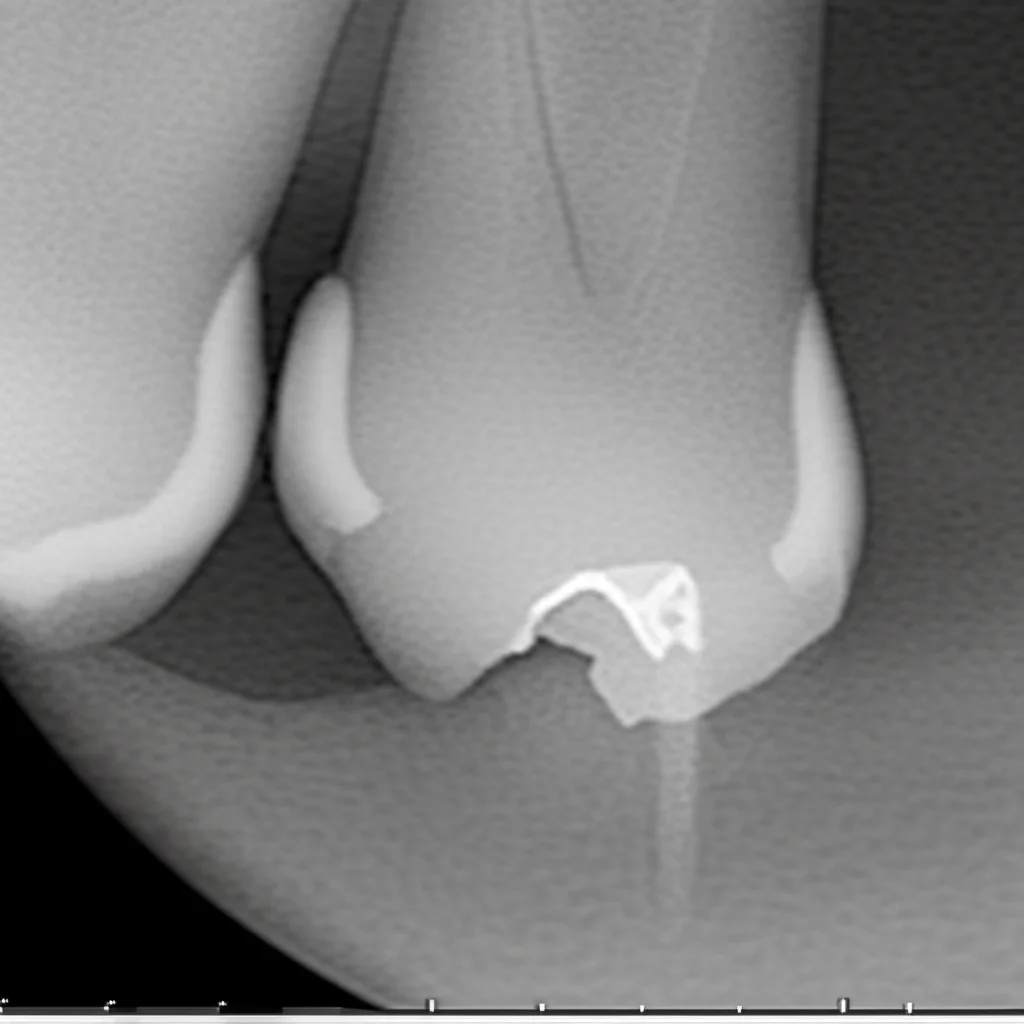

Per valutare i risultati in modo super preciso, i ricercatori non si sono accontentati delle tradizionali radiografie periapicali (le piccole lastrine bidimensionali), ma hanno usato la Tomografia Computerizzata Cone Beam (CBCT). La CBCT è fantastica perché ci dà immagini tridimensionali e permette di misurare il volume esatto delle lesioni, superando i limiti delle radiografie 2D dove le strutture si sovrappongono. Hanno misurato il diametro massimo e il volume delle lesioni all’inizio dello studio e dopo 12 mesi. Inoltre, hanno verificato se i denti trattati rispondevano ai test di sensibilità termica (freddo) ed elettrica, un indizio importante sulla possibile rigenerazione di tessuto vitale.

- Nel gruppo trattato con Coagulo Sanguigno (BC), il volume medio della lesione è passato da 0.33 cm³ a 0.13 cm³. Una riduzione notevole! L’85% dei denti ha mostrato una riduzione della lesione.

- Nel gruppo trattato con Fibrina Ricca di Piastrine (PRF), il volume medio è sceso da 0.27 cm³ a un incredibile 0.04 cm³! Qui, il 100% dei denti ha mostrato una riduzione della lesione.